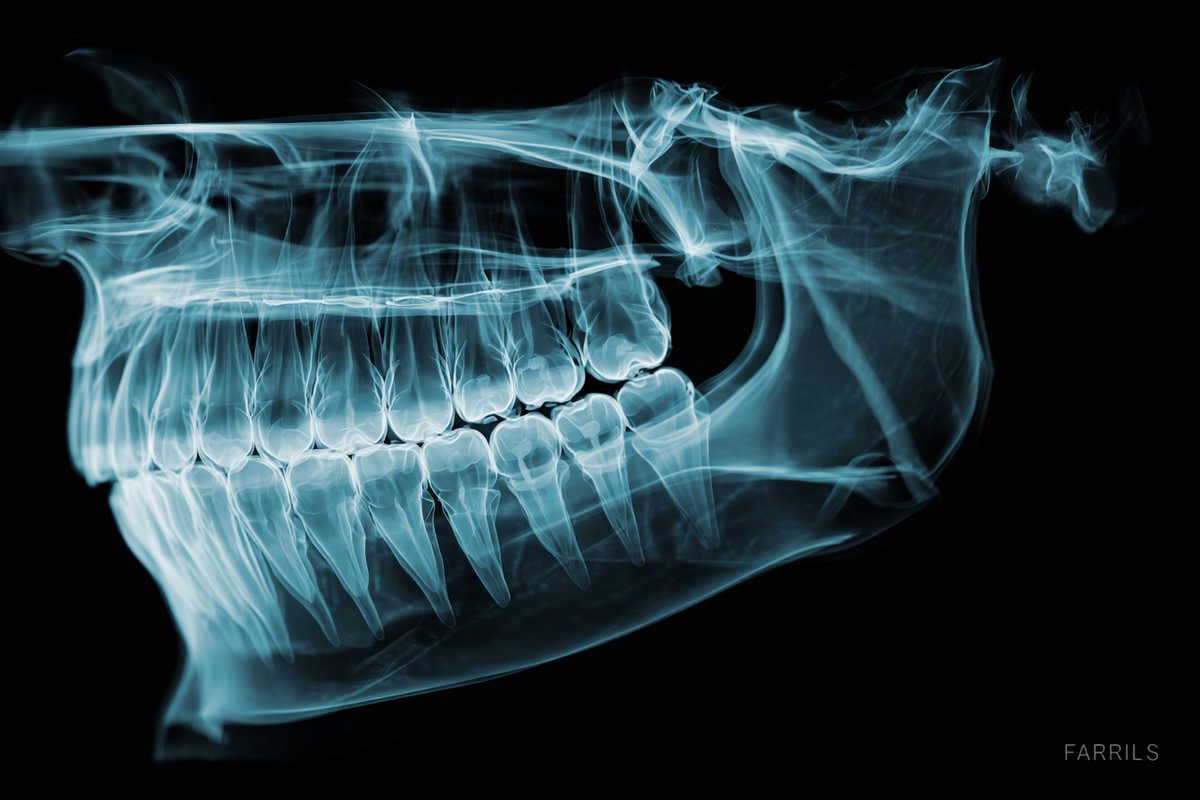

• Exploración clínica, radiografía y TAC 3D para medir y planificar. • Escaneado o impresiones para fabricar los provisionales. • Explicación del plan, tiempos, medicación y cuidados. • Si te preocupa el dolor, se valora sedación consciente para el día de cirugía.